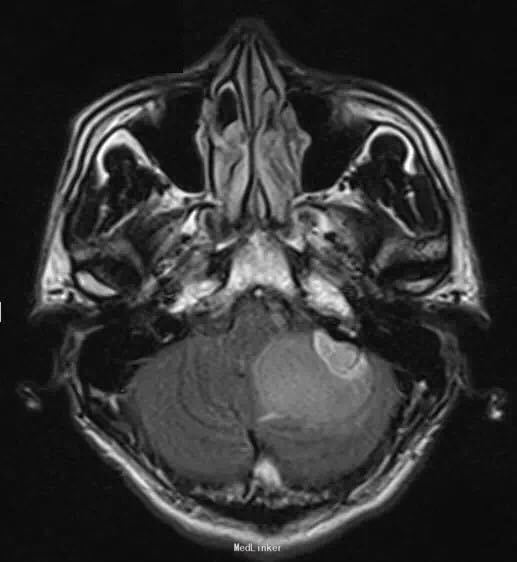

26 岁男性,头疼,恶心,出现加重性嗜睡一个月。

脑 MRI 检查示,左小脑半球一囊性成分为主的病灶,边界清楚,增强扫描见明显强化壁结节。可有轻度血管源性水肿和轻微局部占位效应,临近的四叠体和中脑周围池受压。GRE 序列上未见相关性出血的征象

诊断:小脑血管母细胞瘤。 整块切除 + 术前栓塞术。 可辅助立体定向放射外科技术。